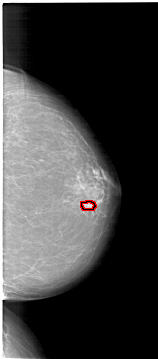

FILE: A_1621_1.RIGHT_CC.OVERLAY

TOTAL_ABNORMALITIES 1

ABNORMALITY 1

LESION_TYPE CALCIFICATION TYPE PLEOMORPHIC DISTRIBUTION CLUSTERED

LESION_TYPE MASS SHAPE LOBULATED MARGINS ILL_DEFINED

ASSESSMENT 4

SUBTLETY 3

PATHOLOGY MALIGNANT

TOTAL_OUTLINES 1

BOUNDARY